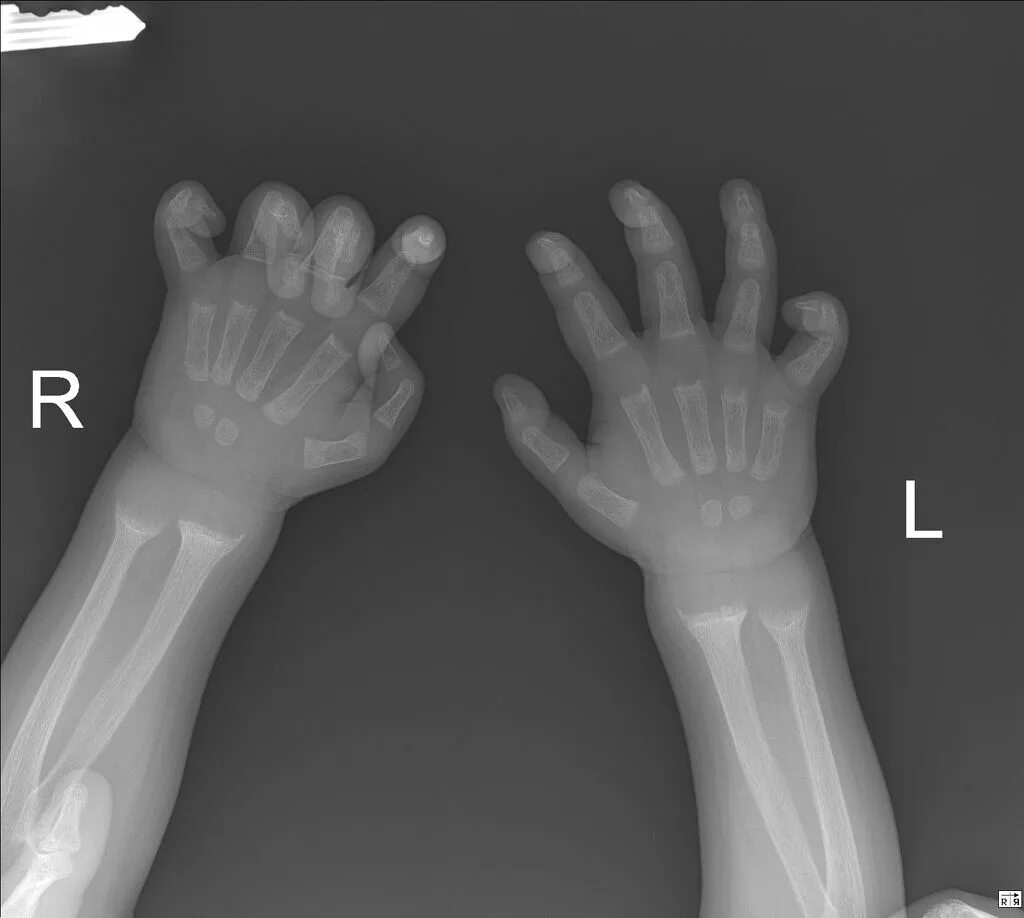

Source x rays